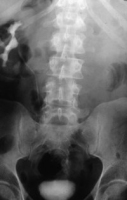

Das Ausscheidungsurogramm ergab eine stumme Niere links (Abbildung 18c). Die retrograde Sondierung zeigte eine deutlische Kompression des Harnleiters sowie eine verkleinerte Niere links mit destruierten Kelchen (Verplumpung) (Abbildung 18d).